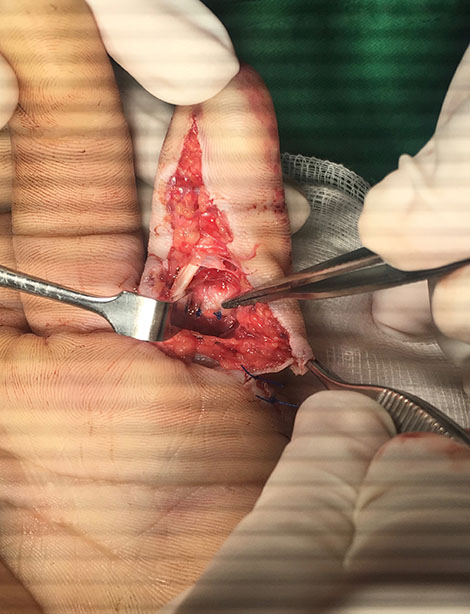

Evalué al paciente y siempre pensando en salvar el dedo de la amputación lo lleve a quirófano ese mismo día en horas de la noche, tras una buena limpieza de las heridas encontramos una luxación del dedo y redujimos la misma reparando la parte ligamentaria, mantuvimos al paciente hospitalizado durante 24 horas en que recibió antibióticos y controlamos el proceso de hinchazón del dedo.